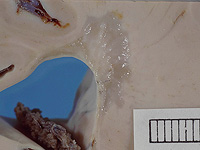

Донор спермы с генной мутацией, радикально повышающей риск развития рака, стал отцом 200 детей по всей Европе. Это выяснилось в ходе масштабного расследования, проведенного крупными вещателями, включая CBS News, BBC News.